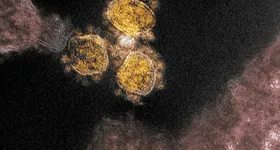

Imaginile pe care le-au prezentat cercetătorii din cele două țări au fost realizate cu ajutorul microscopului electronic în care este surprins atât coronavirusul SARS-COV-2 ce produce boala COVID-19, cât şi celulele infectate şi răspunsul sistemului imunitar.

Astfel, după cum se poate observa în imaginile care au fost colorate, SARS CoV-2 are în exterior o “coroană de țepi”. De altfel, de aici îi vine numele. Aceştia se prind de o enzimă umană numită ACE2, iar compatibilitatea dintre țepișorii virusului și enzima umană este extrem de mare, anunță stirileprotv.ro.